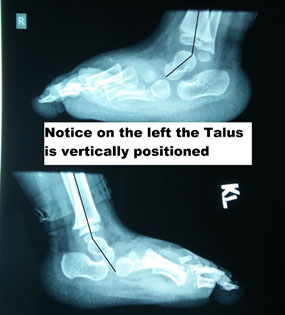

CONGENITAL VERTICAL TALUS (CVT)

CVT is a deformity where there is equinus of the hindfoot and dorsiflexion of the forefoot. The fundamental point of note is the “tightness” of the tissues. This deformity has been called as “rocker bottom foot” or “Persian foot.” It is a very rigid deformity and is almost always a disorder that requires either manipulation or surgical treatment. The difference between the positional calcaneovalgus and CVT is the stiffness in this condition. There is an intermediate entity, which is “Oblique talus,” where there is dorsal displacement of Navicular on the talar head but is still reducible on the talus in plantar flexion. It warrants immediate referral to an orthopedic surgeon and needs a surgical solution. It is usually associated with syndromes like arthrogryposis or myelomeningocele.

A lateral X-ray of the foot will clearly show that the talus is in a vertical position, whereas the relationship in the flexible deformity is anatomical.